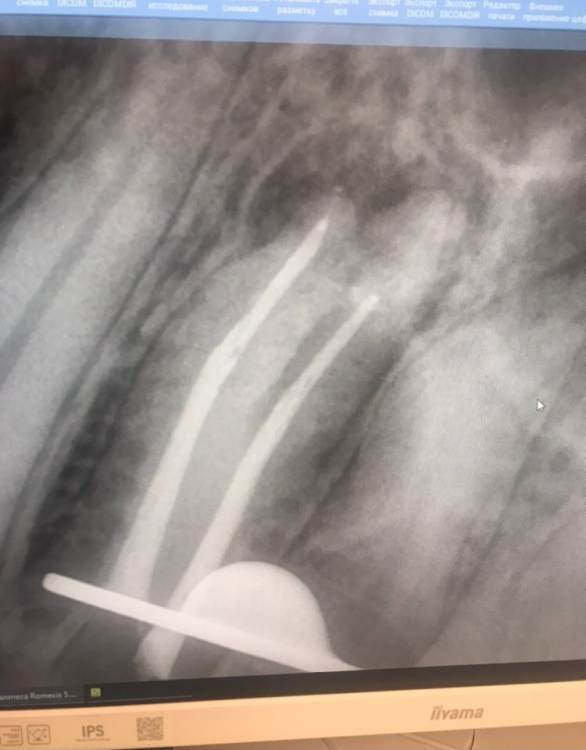

2в июле

длинный корешок, возможно потребуется резекция как сказал доктор ( пройти его не получится тк вышла небольшая перфо)

По поводу кт  - поддерживаю. На том снимке что выложен как контроль не видно верхушек корней и оценить динамику невозможно